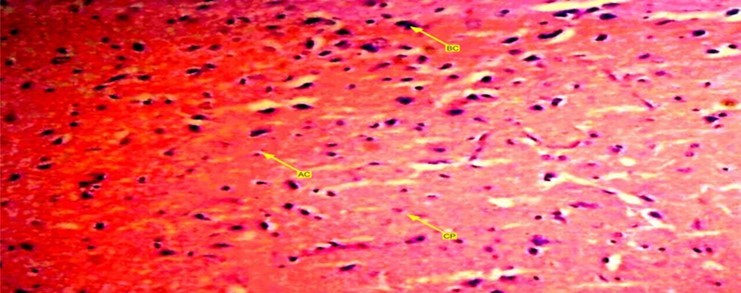

A buffered formalin bottled containing 10% solution was used and preserved the brain tissues of experimental wistar rats. Each bottle was labeled up and allowed to stand for 72 hours in order to ensure maximum penetration. After that, they were placed in ascending dehydration with ethanol solution. First 70% of ethanol solution was used for an hour then subsequent 95% solution and lastly alcohol solution for absolute dehydration. Tissue clearance took place in three (3) subsequent changes of xylene each lasting for 15 minutes. Tissue embedding with paraffin wax was carried out overnight to form blocks which were trimmed and sectioned at 5micro thickness using rotary microtome. Warm water at 28 degree Celsius bathed the tissue samples and dried up on an aluminum glass slides with heamotoxylin and eosin staining method which cleared up 95% of the xylene in alcohol and washed up in running tap water for 15 minutes. The differentiated section o turned blue after addition of 1% alcohol and eosin for 1 minute. The stained sections were viewed under a light microscope and photomicrographs of the stained tissues were taken. Figure 1, Figure 2, Figure 3

Figure 3.A photomicrograph of group three (3), control group showing anterior pituitary gland of female wister rat with arranged gland. Acidophilic, basophilic and chromopobe cells are present in equal proportion.